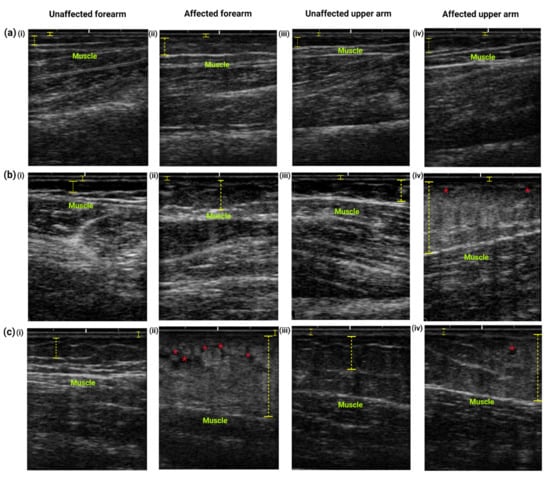

The ultrasound images of the affected and unaffected arms of individuals with different stages of lymphedema display different patterns of tissue structures mainly within the subcutaneous areas (Figure 5). Figure 5a demonstrates thicker subcutaneous layer of the forearm (Figure 5a(ii)) and upper arm (Figure 5a(iv)) area, with limited thickening of the dermis layer when compared to the unaffected arms (Figure 5a(i,iv)). Figure 5b,c represent skin structures of the moderate to severe stage lymphedema. The dermis layer of the unaffected forearm (Figure 5b(i),c(i)) and upper arm (Figure 5b(iii),c(iii)) are hyperechoic (brighter color) whereas the affected forearm (Figure 5b(ii),c(ii)) and upper arm (Figure 5b(iv),c(iv)) show a more hypoechogenic structure (black color), representing typical edema or water retention. Meanwhile, the unaffected forearm and upper arms manifested less echogenicity and a thinner subcutaneous layer. White streaks are prominent in the unaffected area indicating the clear muscle compartment. The subcutaneous layer of the affected forearm and upper arm are hyperechogenic (bright color), indicating the accumulation and penetration of fat and fibrous tissue in the area (cobblestone structure).

Figure 5.

Typical images of ultrasound examination of the (i) unaffected forearm, (ii) affected forearms, (iii) unaffected upper arm and (iv) affected upper arm performed on women with (a) mild and (b,c) moderate to severe stage lymphedema. The structures of the skin measured included the dermis and epidermis layers (yellow straight lines) and the subcutaneous layer (yellow discontinuous lines). The images of the unaffected forearm and upper arm display typical skin structure with normal anatomical structures of the dermis, subcutaneous, and muscle layers. Mild lymphedema is characterized by thickening of subcutaneous layer at the (a(ii)) forearm and (a(iv)) upper arm. In contrast, tissue changes occur mainly at the subcutaneous area, as lymphedema progresses. As demonstrated in (b,c), tissue thickness increased in the affected arms (b(ii,iv) and c(ii,iv)) due to accumulation of fluid in the subcutaneous tissue (indicated by hyperechogenic tissue), which is associated with higher stages of lymphedema. A blurring interface between the subcutaneous and dermis layers is also observed in the affected arms (b(ii,iv) and c(ii,iv)). Prominent subcutaneous edema and fat lobules give the cobblestone or lattice pattern (red asterisks), indicating soft tissue changes that often occur in the subcutaneous layer.